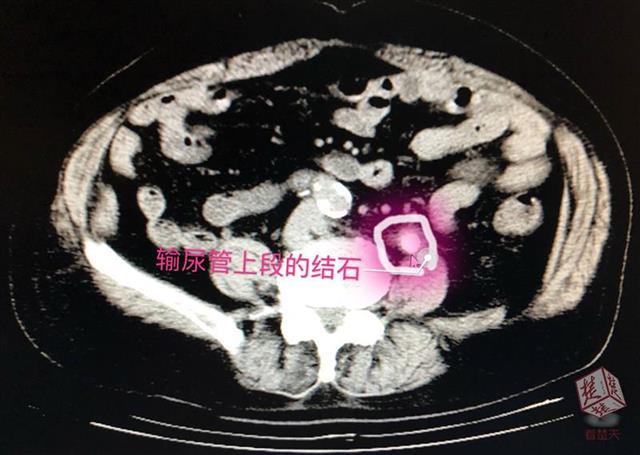

经检查,泌尿外科专家李辉明主任发现,患者左侧输尿管上段被一颗直径约1.2厘米的结石堵住,已出现重度肾积水并感染(肾积脓)。“明明一直在吃排石药,怎么石头还在呢?”老人觉得奇怪。排石药一般都具有利尿、扩张输尿管的作用,服用后原本稳定的肾内结石会随尿液下排,很易在输尿管狭窄处产生滞留,李辉明解释,正是由于赵爹爹的结石卡在了输尿管上段,随着尿液中结晶成分不断附着,结石越变越大,便形成了梗阻。时间长了,尿液排不出去,把肾脏憋成了一个只进不出的“水囊”,目前,积水已达200ml,老人出现的腰痛、高烧、血尿等病症便是结石梗阻产生的急性症状。

当务之急,为解除梗阻,引流肾脏积液避免病情加重引发重度感染危及生命,李辉明建议老人住院,接受左侧经皮肾穿刺造瘘引流,待感染控制后才能进一步碎石取石,进行彻底治疗。